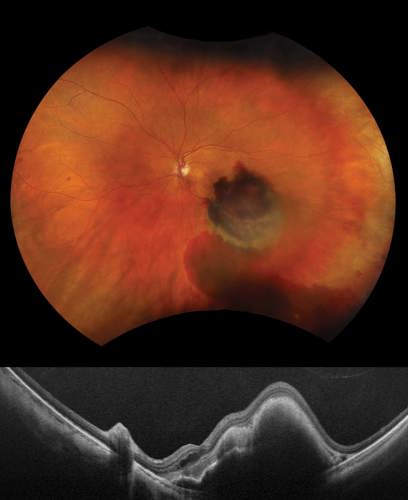

Upon examining the patient, sub-retinal blood within the macula was noted with what appeared to be nodular elevation. Differential diagnosis included retinal arterial macroaneurysm, choroidal mass, or large retinal pigment epithelial detachment (PED). The patient was imaged with the new Silverstone RGB (Optos), a retinal imaging device that integrates true color red-green-blue (RGB) optomap imaging (ultra-widefield [UWF™] retinal imaging) with navigated swept-source optical coherence tomography (SS-OCT), to further investigate and rule out a choroidal mass.

The optomap RGB image captured the extent of the multi-layered hemorrhage extending through the inferotemporal arcade with the true color improving visualization of this complex exudation. Imaging through hemorrhaging and media opacity can be challenging, with ultrasound being the traditional diagnostic tool but requiring specialized clinic resources, time, and patient cooperation. In these cases, Silverstone RGB with UWF and SS-OCT technology allows for efficient, high-resolution, noninvasive, navigable multimodal imaging anywhere on the 200° optomap image. The initial concerns related to nodular elevation from a choroidal mass were relieved with a single 23-mm SS-OCT extended line scan providing the length, depth, and resolution necessary to image through the dense subretinal blood and examine the full extent of the lesion. SS-OCT revealed only subretinal hemorrhage with large PED. Optos UWF angiography showed no evidence of internal circulation or vascular abnormalities characteristic of a choroidal tumor.

Multimodal Optos imaging allowed for quick, easy diagnosis and altered the clinical management of this patient, confirming exudative AMD with active choroidal neovascularization.